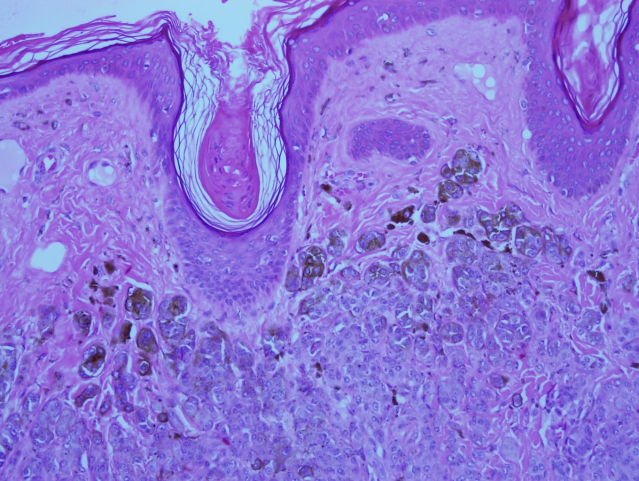

All the specimens collected were sent to the histopathology lab and the report revealed that the specimens had nests and diffusely cellular sheets of benign melanocyte with superficial focal pigmentation and deep dermal maturation. Lateral margins and deeper margins were involved. Overall, there was no malignancy reported (Figure 8 [Fig. 8], Figure 9 [Fig. 9]).

Figure 9: High-power view shows intact dermo-epidermal junction with pigmented melanocytic nests in the superficial part of the nevus.